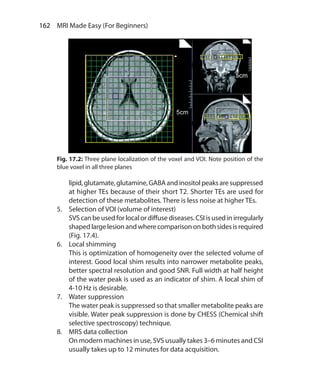

IR sequences are divided based on the value of TI used. IR sequences

can be of short, medium or long TI.

ShortTI IR sequences useTI in the range of 80-150 ms and example

is STIR. In Medium TI IR sequences, TI ranges from 300 to 1200 ms, and

example is MPRAGE (Siemens). Long TI ranges from 1500 to 2500 ms

and example is FLAIR.

SHORT TI (tau) IR Sequence (STIR)

When 90 degree pulse is applied at short TI, LM for all or virtually all

tissues is still on negative side.The tissues with shortT1 have near zero

magnetization, so don’t have much signal. Most pathologic tissues

have increasedT1 as well asT2. Moderately highTE used in STIR allows

tissues with high T2 to retain signals while tissues with short T2 will

have reduced signal.This results in increased contrast between tissues

with short T1-T2 and tissues with long T1-T2. In short TI IR sequences

fat is suppressed since fat has shortT1 (Fig. 5.8). Most pathology appear